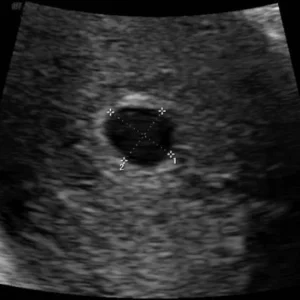

Wk4 Ultrasound